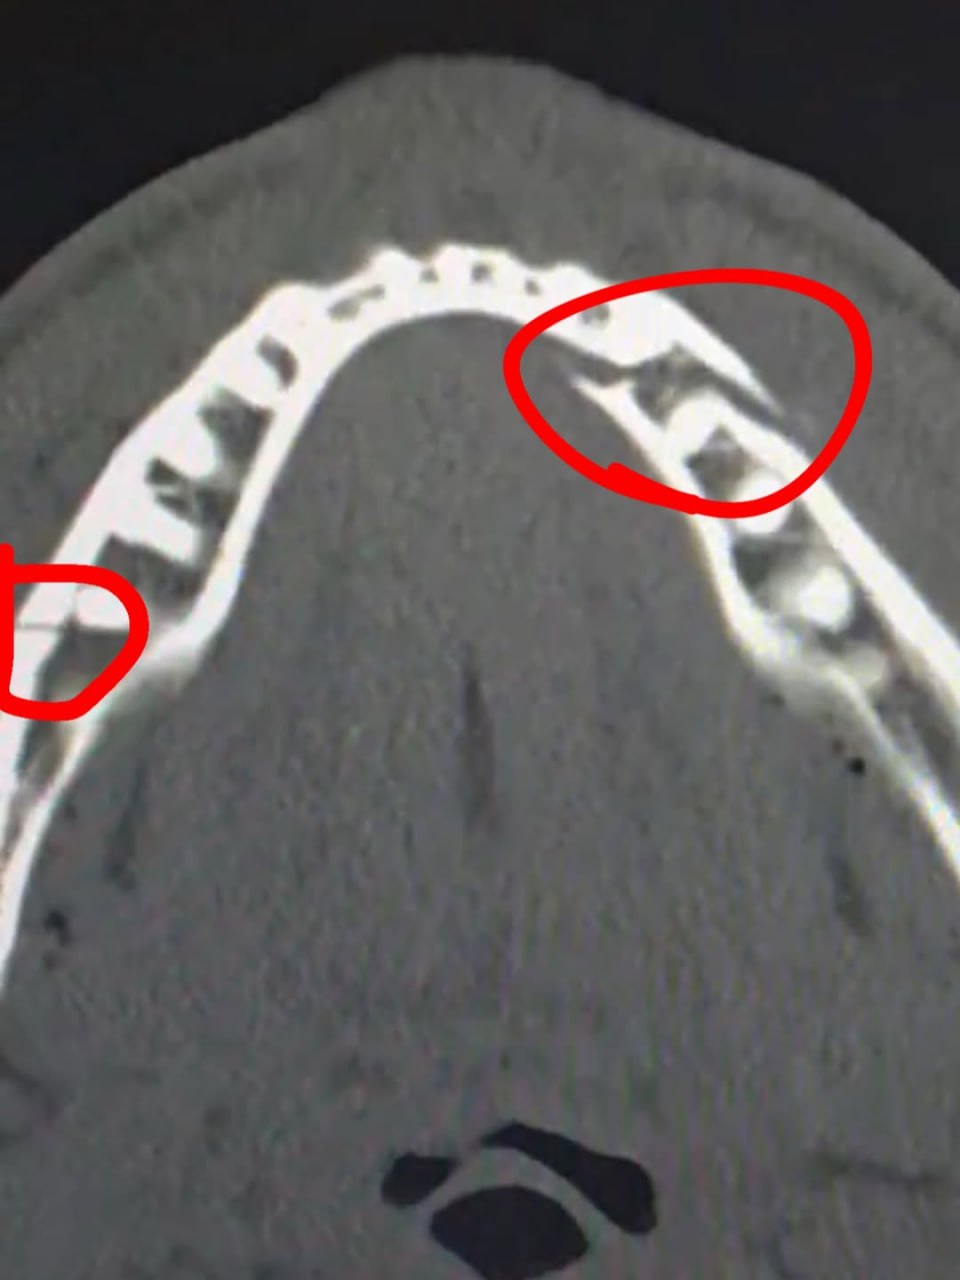

Джейк Пол получил двойной перелом челюсти в бою с Джошуа Блогер Джейк Пол сообщил что сломал челюсть в боксерском поединке против бывшего чемпиона мира в супертяжелом весе Энтони Джошуа Бой прошел в Майами и завершился нокаутом Пола в шестом раунде По ходу поединка блогер дважды побывал в нокдаунах Кажется у меня сломана челюсть Да она точно сломана сказал Пол во время интервью на ринге после боя Бой был крутым мне понравилось Я еще вернусь и хочу стать чемпионом мира Пол не участвовал в послематчевой пресс конференции так как отправился в больницу На видео которое он опубликовал в Instagram принадлежит Meta компания признана экстремистской и запрещена в России видно что задние зубы Пола смещены относительно передних Позднее он выложил рентгеновский снимок травмы Двойной перелом челюсти Дайте мне Канело Сауля Альвареса РБК через 10 дней подписал свой пост Пол Также он выложил ролик с больничной койки соцсети Джейка Пола Подписаться на РБК Спорт